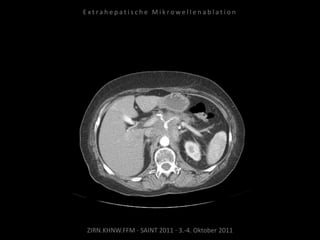

Kontrollbildgebung:

CT 18.08.2010

MRT 08.09.2010

Restvitalität von 2 Metastasen.

Nadelposition unzureichend?